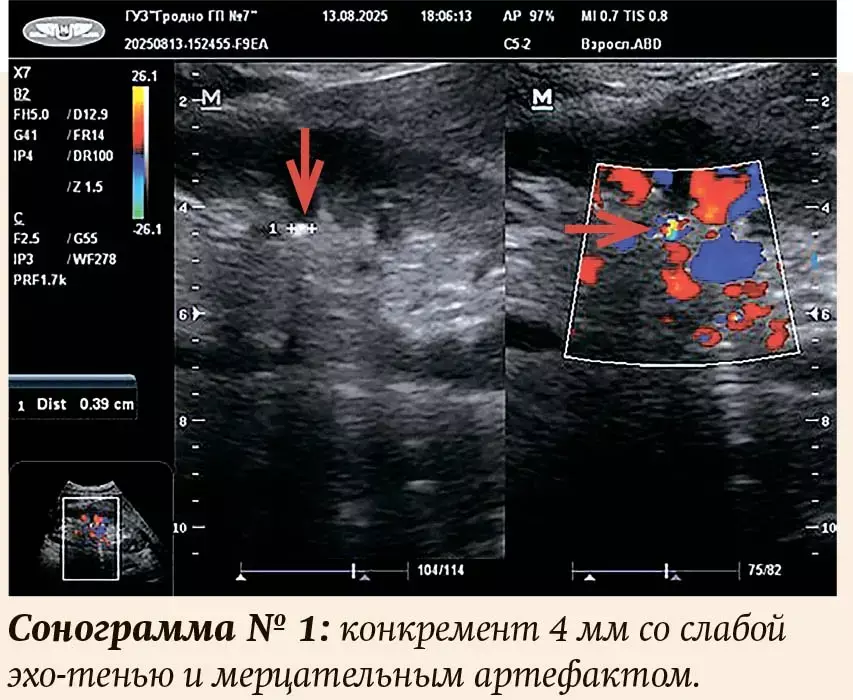

В литературе описан симптом, помогающий определиться с наличием конкремента в собирательной системе почки, называемый «мерцательный артефакт». Он обнаруживается в режиме цветного допплеровского картирования (ЦДК) и возникает при отражении ультразвука от плотной структуры, которым и является конкремент. Артефакт мерцания выглядит в виде быстро изменяющегося пестрого цветового комплекса на уровне конкремента и часто за ним — в виде «хвоста кометы». Диагностическую ценность указанного артефакта изучали многие исследователи, на просторах интернета в базах данных PubMed, еLibrary, Web of Science, Cochrane Library и других можно найти сотни статей на эту тему. Из своего личного опыта знаю: данный признак часто (но тоже не всегда) значительно повышает возможность обнаружения камня при невозможности его четкой визуализации или при небольших размерах.

В статье А. И. Громова говорится о том, что можно увидеть мерцание от камней почек, размеры которых составляют даже 1 мм. При этом описаны ситуации, когда мелкие конкременты отчетливо выявляются при УЗИ и в то же время упускаются при КТ-исследовании.

Кроме того, существуют указания, как в отечественной литературе, так и в зарубежной, что интенсивность артефакта зависит от физических свойств поверхности конкремента. Так, камни с гладкой поверхностью (моногидрат оксалата кальция и ураты) не формируют «мерцательный артефакт», и наоборот — конкременты с рыхлой кристаллической поверхностью (дигидрат оксалата кальция и фосфаты) дают интенсивное «мерцание». Физическая характеристика камня может быть важна для выбора способа лечения МКБ.

Размеры выявленных конкрементов — от 3,5 до 25 мм (см. примеры на сонограммах), причем у 5 пациентов (4,7 %) размер не превышал 4 мм. Во всех случаях даже при небольших размерах присутствовали все эхографические признаки конкремента, включая акустическую тень, иногда очень слабую, и/или мерцательный артефакт. Количество разнообразное — от одного до нескольких. Единичный конкремент присутствовал у 55 человек (51 %), у двух (2 %) — коралловидный, остальные имели 2 и более камней. У двух пациентов были выявлены признаки нефрокальциноза. У одной пациентки (57 лет) с несколькими конкрементами в обеих почках и рецидивирующим течением подтверждено наличие аденомы околощитовидной железы. У троих мужчин (2,8 %) с гиперплазией предстательной железы обнаружены камни в мочевом пузыре. Таким образом, проанализировав собственные данные, можно сделать вывод: полученные результаты соответствуют общемировой статистике.